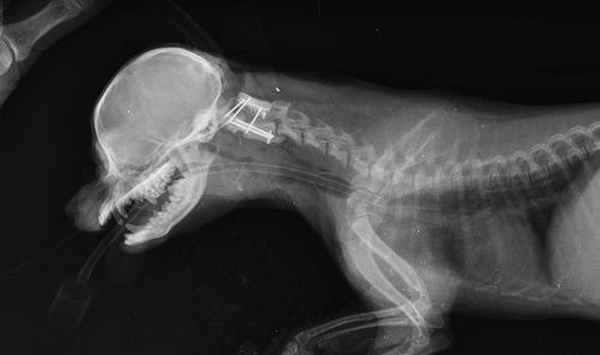

В клинике «Самарская Лука» используется хирургическая коррекция данной патологии с помощью вентральной стабилизации С1-С2 реперными или спицами Киршнера с последующей их фиксацией костным цементом.

Техника артродеза атланто-аксильного сустава включает трансартикулярную фиксацию, установку 3 имплантов с закреплением костным цементом. Суставные хрящи удаляются, производится тракция и репозиция компонентов сустава, после чего последовательно, устанавливаются 3 спицы через сустав С1-С2 и в тело С2. Закладку аутотрансплантанта, равно как и шейные послеоперационные корсеты мы не используем.

Краниография собаки с вентральной стабилизацией С1-С2.

Интраоперационное - вентральная фиксация спицами Киршнера первого и второго шейного позвонка.

Укрытие металла костным цементом